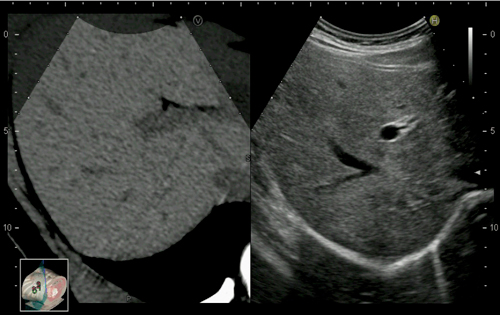

RVS臨床画像

CT/MRI/USのボリュームデータを基にして,超音波診断装置の

プローブの位置と角度に応じたMPR画像をリアルタイムに表示する。